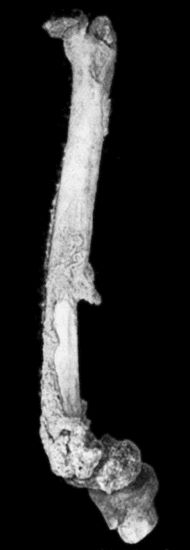

| 118. | Shaft of the Femur after Acute Osteomyelitis | 444 |

| 119. | Femur and Tibia showing results of Acute Osteomyelitis | 445 |